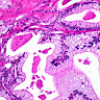

Para entender la función de los órganos y sistemas, el conocer la forma ayuda a integrar ambos conocimientos. Saber la forma de las células, la integración en tejidos y de éstos a órganos, permiten al estudiante de medicina, en su momento, y al médico posteriormente, comprender qué es lo que está ocurriendo en su paciente.

Para ciertas áreas de la medicina, la morfología es muy importante: en el caso de la hematología, la base para el diagnóstico, es el estudio morfológico de la biopsia de médula ósea o el frotis de sangre periférica. Para ciertas patologías renales, es necesaria la biopsia, y de igual manera para la patología pulmonar.

No se diga en el caso de las neoplasias, lo importante que es conocer lo normal y anormal.